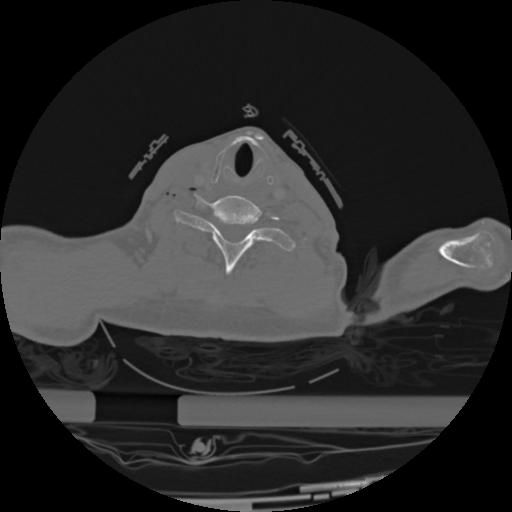

22 ANGIO,CE,Vol,0.5,ANGIO,,